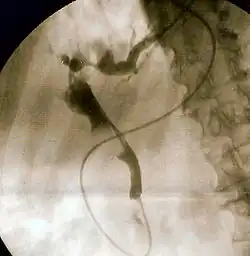

Cholangiogram through a nasobiliary drain showing the common bile duct in black (diagonally from top left to bottom right in the center) with an interruption in the contour due to a large gallstone.

Given that ascending cholangitis usually occurs in the setting of bile duct obstruction, various forms of medical imaging may be employed to identify the site and nature of this obstruction. The first investigation is usually ultrasound, as this is the most easily available.[1] Ultrasound may show dilation of the bile duct and identifies 38% of bile duct stones; it is relatively poor at identifying stones farther down the bile duct. Ultrasound can help distinguish between cholangitis and cholecystitis (inflammation of the gallbladder), which has similar symptoms to cholangitis but appears differently on ultrasound.[14] A better test is magnetic resonance cholangiopancreatography (MRCP), which uses magnetic resonance imaging (MRI); this has a comparable sensitivity to ERCP.[14] Smaller stones, however, can still be missed on MRCP depending on the quality of the hospital's facilities.[1]

The gold standard test for biliary obstruction is still endoscopic retrograde cholangiopancreatography (ERCP). This involves the use of endoscopy (passing a tube through the mouth into the esophagus, stomach and thence to the duodenum) to pass a small cannula into the bile duct. At that point, radiocontrast is injected to opacify the duct, and X-rays are taken to get a visual impression of the biliary system. On the endoscopic image of the ampulla, one can sometimes see a protuberant ampulla from an impacted gallstone in the common bile duct or the frank extrusion of pus from the common bile duct orifice. On the X-ray images (known as cholangiograms), gallstones are visible as non-opacified areas in the contour of the duct. For diagnostic purposes, ERCP has now generally been replaced by MRCP. ERCP is only used first-line in critically ill patients in whom delay for diagnostic tests is not acceptable; however, if the index of suspicion for cholangitis is high, an ERCP is typically done to achieve drainage of the obstructed common bile duct.[1]